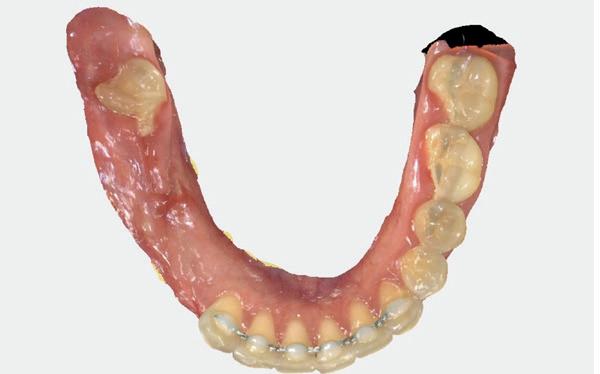

Edentate onderkaak

Tristan: “De steilheid van de leercurve is nu anders dan toen ik begon, omdat we meer weten en de technieken verder zijn ontwikkeld met onder andere boorprotocollen en hechttechnieken. In relatief korte tijd kun je jezelf nu het zetten van implantaten eigen maken. De edentate onderkaak is daarbij een mooie start. Je kunt meters maken, in onder andere prepareren en hechten, met een eenvoudige ingreep zonder esthetische risico’s te nemen. Je krijgt ook meer inzicht in implantaatsystemen, weke delen en bot. Deze mooie start in de implantologie staat echter onder druk. De verzekeraars willen dat alleen NVOI geregistreerde implantologen edentate onderkaken behandelen. Of dat er een geregistreerd implantoloog op de achtergrond aanwezig is. Naar mijn mening staat dat de ontwikkeling van tandartsen die zich willen ontwikkelen in de implantologie in de weg. Dat dit voor de bovenkaak geldt kan ik achter staan, maar voor de onderkaak vind ik dat niet nodig.”

Gijs: “De beperking van de zorgverzekeraar maakt het voor jonge tandartsen inderdaad moeilijker om vlieguren te maken en te beginnen met implanteren. Scholing en meekijken is toch anders dan het zelf doen. Tennis leer je ook door op de baan te staan, veel over te slaan en zo balbeheersing te krijgen. Natuurlijk zijn scholing en meekijken noodzakelijk in het traject, maar daarna moet je wel onder begeleiding van een mentor aan de slag. Edentaat is dan echt geen eenvoudige ingreep, maar het gaat erom dat de risico’s zeker op esthetiek lager zijn.

Je hebt meer marge op resultaat. Uiteraard zou ik er dan voor kunnen kiezen NVOI geregistreerd te worden, daar denk ik ook over na, maar dat is een behoorlijk traject. Het zou mooi zijn om daarvoor al zelfstandig te kunnen implanteren op bijvoorbeeld een onderkaak. Op weg naar volledige erkenning kan ik hier intern prima implanteren zonder zelf geregistreerd te zijn.